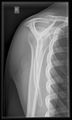

أشعة إكس

-

CR. shoulay film.

Transaxillary conventional radiography

Y-projection conventional radiography